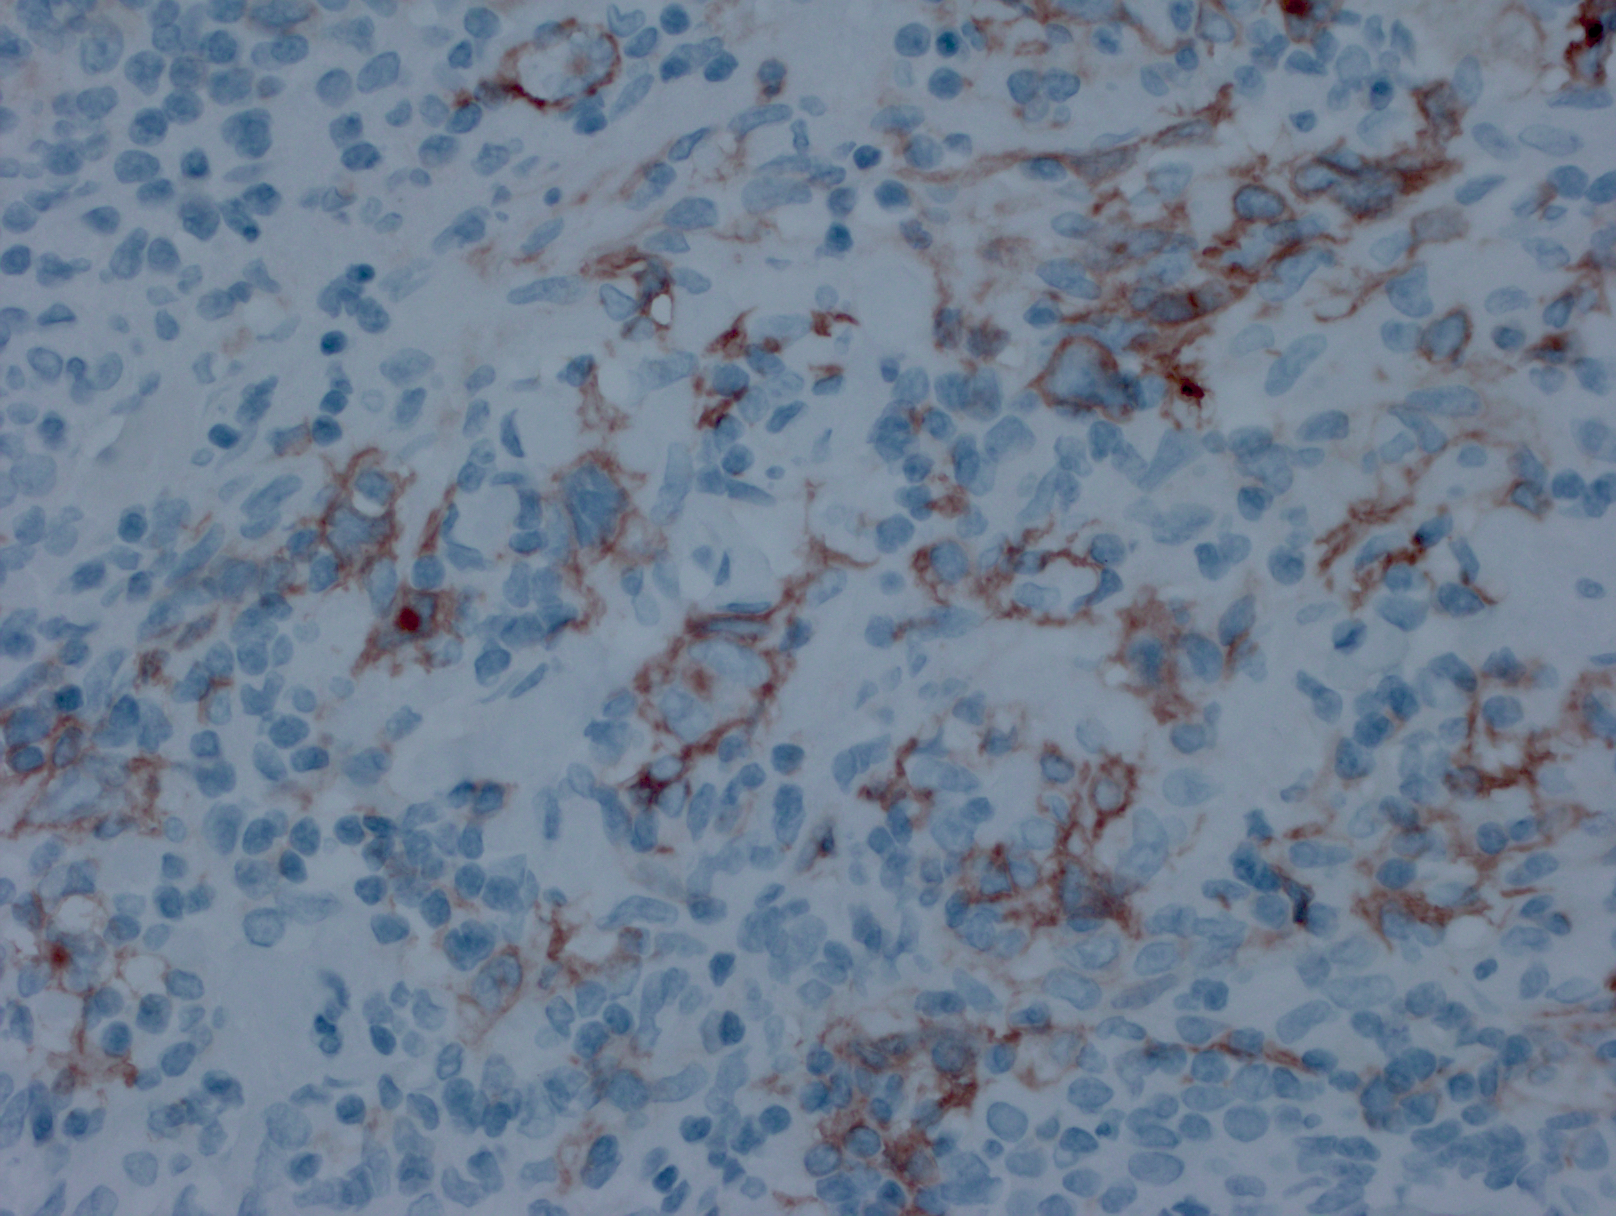

免疫表型:肿瘤细胞表达“混合”抗原,符合弥漫大 B 细胞淋巴瘤和经典霍奇金淋巴瘤的双重特征。CD45+,CD30+,多数 CD15 阳性,CD20 和 CD79a 通常阳性,PAX5. Oct2. 和 BOB1 一般也阳性。Bcl-6+/-, CD10-。 EBER 一般阴性(但也有极少阳性病例报道)。

免疫组织化学染色:

肿瘤细胞表达“混合”抗原,符合弥漫大 B 细胞淋巴瘤和经典霍奇金病的双重特征。CD45+,CD30+,多数 CD15 阳性,CD20 和 CD79a 通常阳性,PAX5. Oct2. 和 BOB1 一般也阳性。Bcl-6+/-,CD10-。EBER 一般阴性。